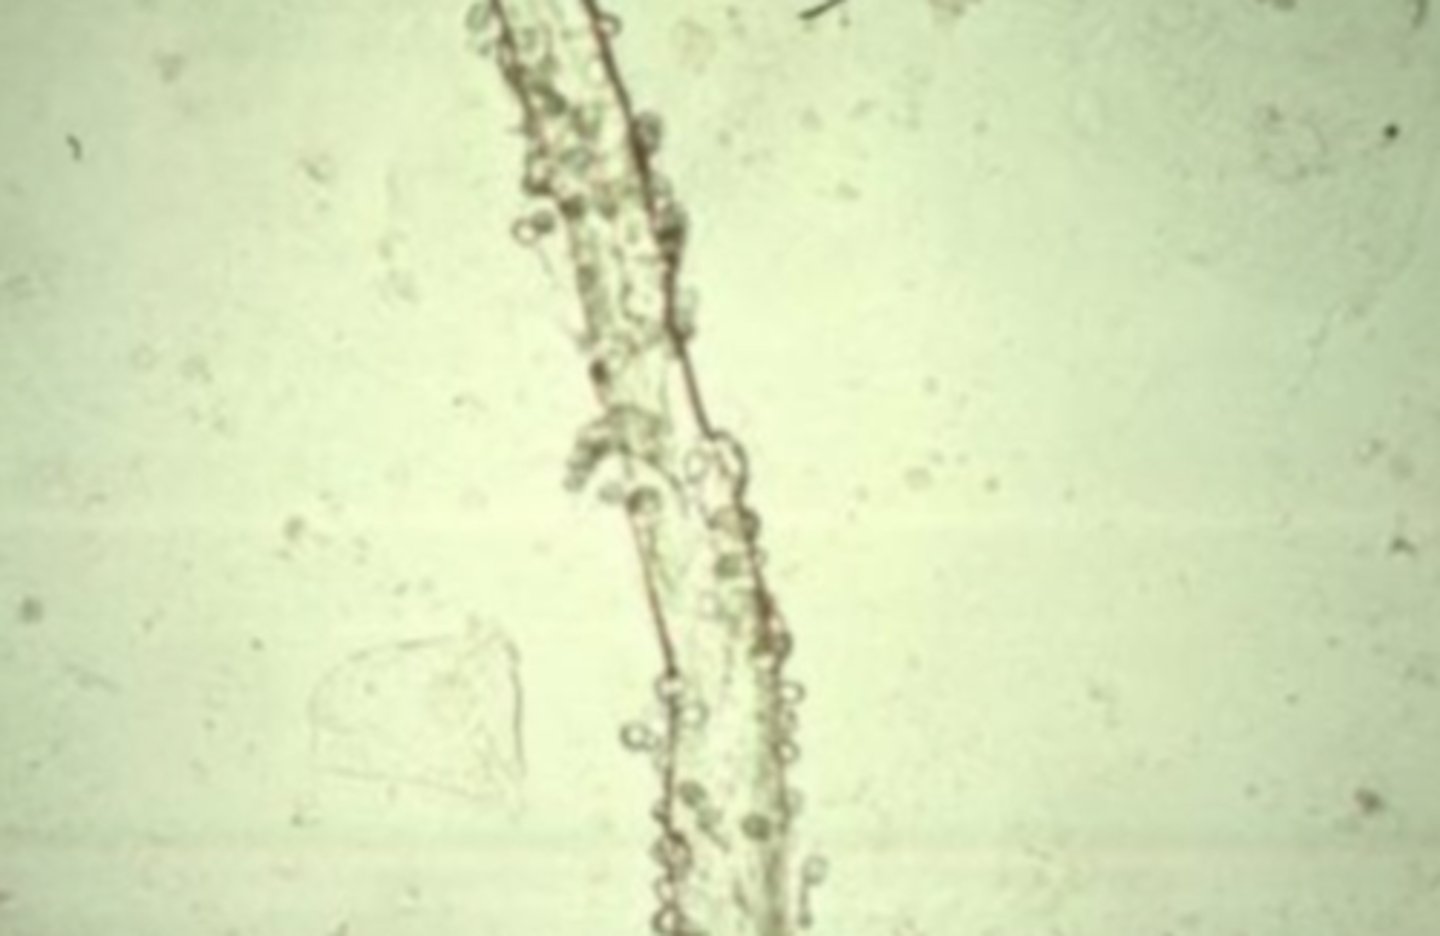

Mucus Threads

semi-transparent under brightfield microscopy and could be mistaken for hyaline casts. They are ribbon-like strands with poorly defined edges, pointed or split ends, and longitudinal striations.

<p>semi-transparent under brightfield microscopy and could be mistaken for hyaline casts. They are ribbon-like strands with poorly defined edges, pointed or split ends, and longitudinal striations.</p>